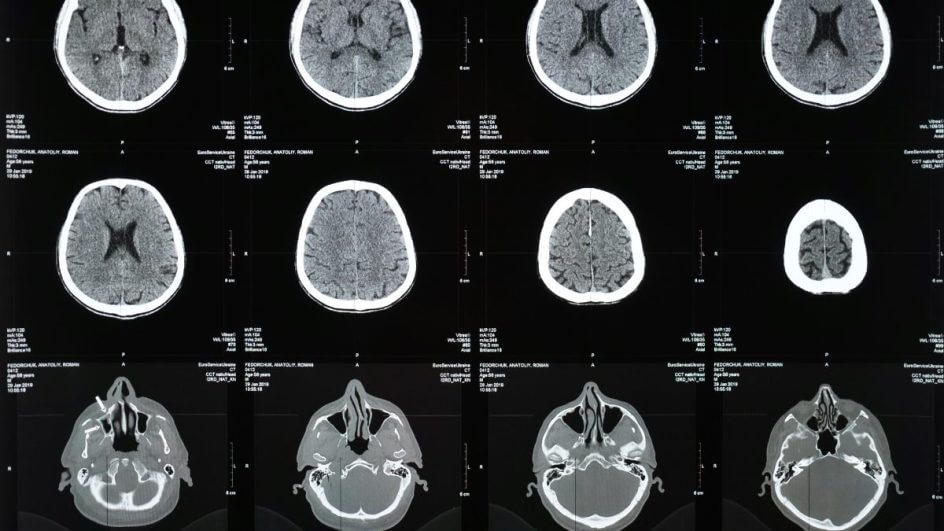

Pesquisadores da Universidade Baylor em Waco, Texas, descobriram que não apenas o C. albicans pode entrar no cérebro, como também produz compostos tóxicos chamados peptídeos, frequentemente associados à doença de Alzheimer.

— Descobrimos que o C. albicans produz enzimas chamadas proteases aspárticas secretadas que rompem a barreira hematoencefálica, permitindo ao fungo acesso ao cérebro, onde causa danos —, acrescentou Wu.

A ideia predominante no meio médico, é que esses peptídeos que são produzidos de forma natural pelo próprio cérebro, também são responsáveis por ativar células cerebrais que mantêm a quantidade de fungos em níveis baixos, porém, não eliminam completamente a possibilidade de infecção fúngica.